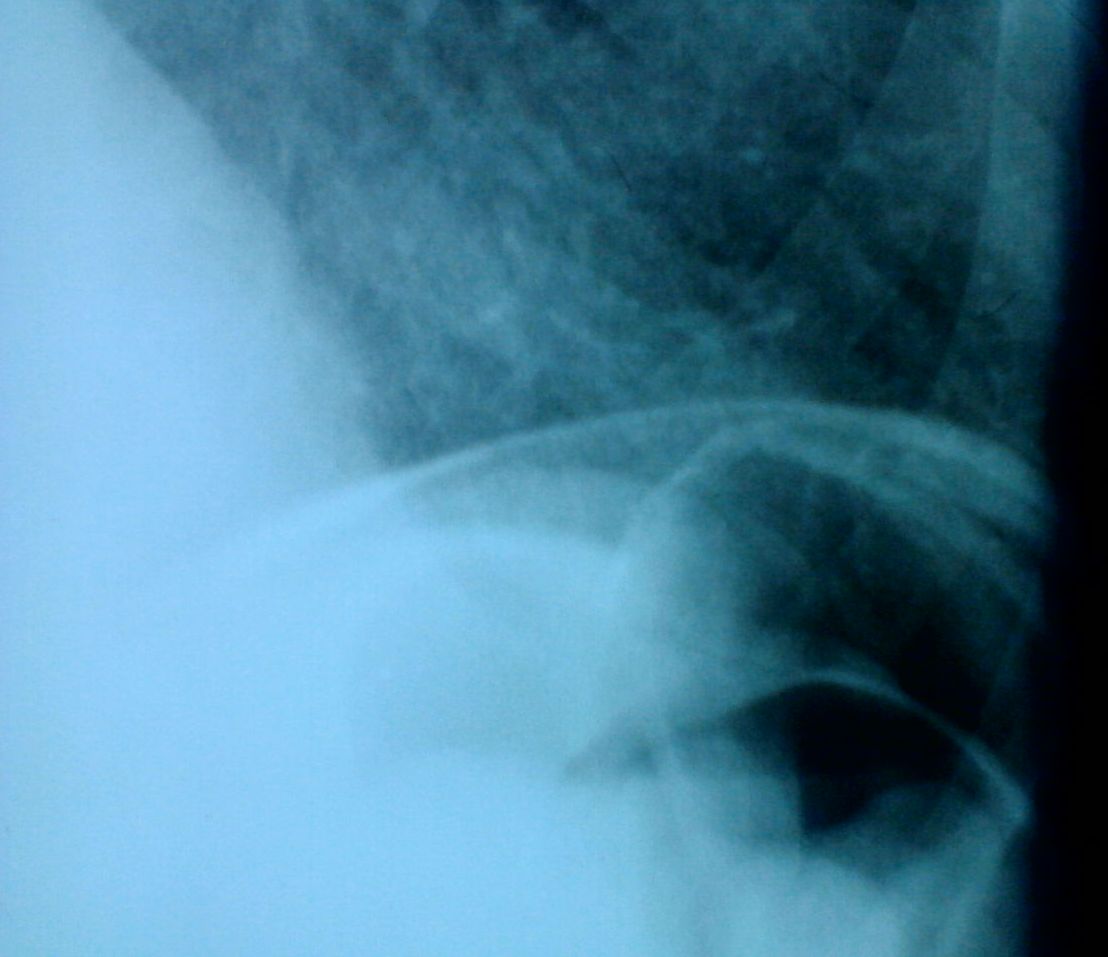

Пневмоперитонеум (классика жанра)

Ургентный пациент.

Показательная классика.

Прободная язва по малой кривизне препилорического отдела желудка.(На практике убедилась, что газ под обоими куполами обычно даёт перфорация желудка, а 12-перстная -под правым купололм)

Александр, считать как-то некогда было (да и не люблю я её, статистику). Но так уж по жизни складывалось: вижу газ под обоими куполами, загадываю на желудок. Подтверждается. Один раз только оказалась перфорация толстой кишки.